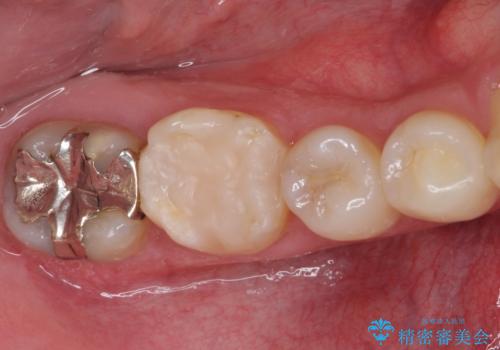

- 右下奥歯の虫歯がしみて痛いとのことで来院された患者様です。

神経近くにまで及ぶ大きな虫歯でしたが、速やかに処置を行い、痛みは即日解消されました。

虫歯が大きかったため、クラウンによる補綴治療が必要になる旨をお伝えしたところ、矯正治療にも興味があるとのことでした。

短期間で手間のかからない方法がご希望でしたので、ワイヤー装置による矯正治療を行うこととし、矯正治療後に右奥2歯をセラミッククラウンにて補綴することとしました。

セラミッククラウンによる補綴治療と矯正治療の双方が必要となる場合、矯正治療前の処置や歯の移動中に必要な処置など、二種類の治療を同時にチェックすることがとても重要となります。

当法人では、1つの医院で全ての診療を進めることができるため、このような方には大変お勧めです。